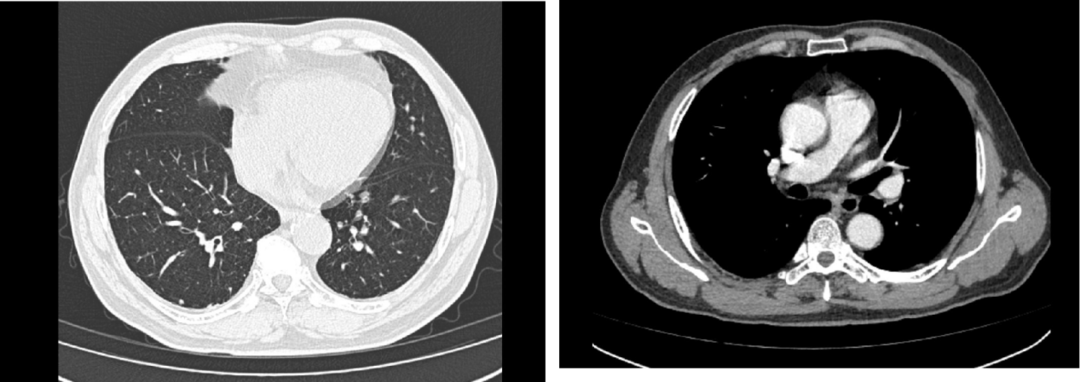

随着免疫治疗的发展,PD-1单抗在包括肺癌、胃癌、食管癌、鼻咽癌等在内的多种实体瘤的治疗中表现出令人鼓舞的治疗潜力,并随着临床证据的积累,发挥着越来越重要的治疗价值。同时,PD-1单抗在局部晚期肺鳞癌患者的新辅助治疗中的价值,也得到临床的积极探索。本期,我们分享一例局晚期肺鳞癌同时合并鼻咽癌的患者接受替雷利珠单抗联合化疗新辅助治疗后,顺利实施肺癌根治术,且鼻咽癌病灶也得到一定缓解的病例。 | 病例提供者:复旦大学附属中山医院厦门医院 王仁峰医生 王仁峰 主治医师 硕士研究生 复旦大学附属中山医院厦门医院 胸外科 中国胸外科三维重建及人工智能联盟常务委员 中国转化医学联盟胸部肿瘤外科专业委员会委员 河北省急救医学会第一届胸外科专业委员会青年委员 河北省健康学会胸外科管理分会第一届委员 河北省呼吸与健康学会微创外科分会委员 一般资料:男性,61岁。 主诉:因“确诊肺恶性肿瘤3月余”入院。 现病史:患者于2020-11-25因咳血就诊厦门市第三医院,查胸部CT示:右肺下叶后基底段见一实性结节,大小约27.6*23.7 mm,纵隔内见多发淋巴结。2020-11-26行支气管镜检查,病理示右下肺低分化鳞癌。 后转诊我院,2020-12-03行PET-CT示:右下肺后基底段代谢增高,符合肺癌并纵隔(7,10R组)多发淋巴结转移;鼻咽部软组织明显增厚,双侧咽旁间隙,右侧颈部区多发肿大淋巴结,鼻咽恶性肿瘤可能。头颅增强MRI结果提示:鼻咽软组织增厚,其余未见明确转移灶。2020-12-04在我院行超声支气管镜(EBUS),术后病理(2020-12-07)示第7组,第10组淋巴结转移性低分化鳞状细胞癌。2021-12-09于我院耳鼻喉科行局麻鼻咽活检术,术后病理(2020-12-15)示:鼻咽部非角化性癌,未分化型;建议先行肺癌新辅助治疗后再行鼻咽部放疗。 既往及个人史:高血压病史8年;口服药物治疗,血压控制可。 影像学检查: 胸部平扫(2020-12-03):右肺下叶见结节状软组织密度影,范围约22×17mm,邻近支气管腔闭塞;右肺中叶及下叶见微小实性结节影(Se5 Im199、217),直径约4-5mm;两肺透亮度稍增强,两肺散在条索影;纵隔内见肿大淋巴结,短径约14mm;胸膜无增厚,胸腔内无积液。影像学诊断:右肺下叶MT机会大,纵隔淋巴结肿大;右肺微小结节,有待随访;轻度肺气肿;两肺少许慢性炎症。见下图: 鼻咽部病理报告(2020-12-10): 鼻咽部组织:灰白灰褐色碎组织,共计直径0.8cm。(鼻咽部组织)送检破碎黏膜组织慢性炎,局部固有膜内见上皮样细胞巢,伴较多炎性渗出坏死物,正在行免疫组化检查以协助诊断。 2020-12-15补充报告:(鼻咽部组织)镜下见少量破碎黏膜组织及较多坏死物,其黏膜固有膜内散在少许上皮样细胞巢,伴细胞异型,免疫组化标记示少许上皮样细胞P63、P40及EBER阳性,部分异型上皮样细胞及上皮标记表达不理想。结合同一病例20AS06823,本例考虑为非角化癌,未分化型。免疫组化(2020-N02641):20AS06945-001: CK7(少量+),p40(部分+),p63(部分+),Ki-67(70%阳性),EGFR(+),CK{pan}(少量+),TTF-1(8G7G)(-);NapsinA(-),EBER(+),CD56(-),CD3(部分淋巴细胞+),Perforin(-),GranB(-),TIA-1(-),CD30(少量+)。 MRI颈部软组织平扫+增强+DWI(2020-12-18): 鼻咽部MRI示鼻咽右侧壁及后壁软组织不规则增厚,咽隐窝消失,增强后可见轻度异常强化,双侧鼻咽旁间隙见肿大淋巴结,较大者位于右侧,最大层面约23 mm×21 mm×35 mm,双侧颈部多发小淋巴结,双侧海绵窦无受侵表现,部分副鼻窦黏膜增厚。 诊断:右下肺恶性肿瘤(鳞癌 cT1cN2M0 ⅢA期)、鼻咽癌、高血压 第一阶段:新辅助免疫联合化疗治疗 治疗方案:患者于2020-12-18至2021-01-09接受“替雷利珠单抗200 mg+紫杉醇(白蛋白结合型)400mg+d1卡铂450mg”2个周期。治疗过程顺利,无严重不良反应。 复查胸部CT(2021-02-01):原2020-12-03片右肺下叶结节,此次未见,纵隔淋巴结稍大,较前片相仿,右肺微小结节,较前相仿,轻度肺气肿;两肺少许慢性炎症。 疗效评价:部分缓解。 继续治疗:患者继续接受“替雷利珠单抗200 mg+紫杉醇(白蛋白结合型)400mg+d1卡铂450mg”治疗至2021-02-23,共治疗4个周期。治疗过程顺利,无严重不良反应。 复查胸部CT(2021-03-16):两肺见小实性结节影(Im34、38、43),直径约4-5 mm;两肺透亮度稍增强,可见小囊样影,两肺散在条索影,增强后未见异常强化灶,纵隔内见稍肿大淋巴结,短径约13mm;胸膜无增厚,胸腔内无积液。影像学诊断:符合右肺MT治疗后改变,两肺小结节,较前片(21-02-01)相仿,轻度肺气肿;两肺少许慢性炎症。提示纵隔淋巴结较前缩小,建议手术治疗。见下图: 第二阶段:手术治疗 患者于2021-04-02,在全麻下行(右侧)经胸腔镜右下肺癌根治术。 术后病理(2021-04-02): (1)右肺下叶切除标本:大小17*8*2.5cm,支切直径1.5cm,距段支切1cm、距表面胸膜0.1cm见一扎线,扎线处见一灰红质稍实区,范围1.5*1.2*1cm,质软,界不清。病理诊断:(新辅助化疗联合免疫治疗后,右肺下叶切除标本)镜下肺组织部分区肺泡腔塌陷伴纤维组织增生及炎症细胞浸润,考虑为炎症性病变。检出支气管旁淋巴结12枚,均呈慢性炎症,其中1枚淋巴结内见组织细胞反应伴坏死及胆固醇结晶形成。 (2)送检分组淋巴结:2.4组淋巴结、7组淋巴结、10组淋巴结、11组淋巴结。病理诊断:送检2.4组淋巴结2枚,均呈慢性炎。送检7组淋巴结9枚,均呈慢性炎,其中2枚淋巴结内见泡沫样组织细胞反应伴胆固醇结晶形成。送检10组淋巴结1枚,呈慢性炎。送检11组淋巴结5枚,均呈慢性炎。 (3)术后病理结果回报(新铺助化疗联合免疫治疗后,右肺下时切除标本)镜下肺组织部分区肺泡腔塌陷伴纤维组织增生及炎症细胞浸润,考虑为炎症性病变(ypTONOMO)。 疗效评估:PCR(病理完全缓解) 第三阶段:肺癌根治术后复查及鼻咽癌处理 肺癌根治术后复查: 胸部CT平扫(2021-5-8):右肺术后,右肺下叶见片絮状磨玻璃密度影,两肺见多枚小结节(im19、29、35、45等),大者直径约4-5mm,所见各支气管腔通畅,肺门及纵膈未见肿大淋巴结,胸膜无增厚,右侧胸腔内见少量积液及积气。右心膈角见稍大淋巴结。影像学诊断:右肺术后,右肺下叶少许炎症,右侧胸腔少量积液、积气,随访;余两肺多发小结节,较前大致相仿,密切随访。右心膈角稍大淋巴结。 鼻咽癌影像学随访: 头部MRI检查(2021-5-11):鼻咽部平扫+增强。结果提示,患者鼻咽右侧壁及后壁软组织稍厚,增强后明显均匀强化,双侧咽旁间隙、胸锁乳突肌深面见多发小及稍肿大淋巴结,较大者约8×8mm,增强后部分呈轻度强化,部分呈明显强化,双侧海绵窦无受侵表现,部分副鼻窦黏膜增厚。影像学诊断:患者为鼻咽癌MT病例:鼻咽右侧壁及后壁稍厚,颈部淋巴结转移,较2020-12-18片病灶及淋巴结均明显缩小,轻度鼻窦炎。疗效评估:PR。 下一步治疗:免疫维持治疗 1. 患者因诊断肺恶性肿瘤入院,经进一步检查后,明确肺鳞癌分期为cT1cN2M0 ⅢA期,同时发现患者存在鼻咽癌病灶。经过多学科讨论后,决定对患者先行肺癌新辅助治疗后再行鼻咽部放疗。 2. 患者先后共接受4个周期的新辅助化疗联合免疫治疗,具体方案为替雷利珠单抗+紫杉醇(白蛋白结合型)+卡铂,治疗过程顺利。影像学复查结果提示,患者纵膈淋巴结较前缩小,可接受手术治疗。 3. 患者如期接受胸腔镜右下肺癌根治术,术后病理提示疗效评估达pCR。术后1月余患者接受胸部影像学复查提示,患者两肺情况较前大致相仿。鼻咽部影像学复查提示,患者鼻咽癌病灶及淋巴结均较之前明显缩小,治疗效果达PR。 范虹 医学博士,复旦大学附属中山医院胸外科主任医师,硕士研究生导师 复旦大学附属中山医院厦门医院大外科主任兼胸外科执行主任 美国哈佛医学院麻省总院research fellow da Vinci Surgical System机器人系统Console Surgeon 上海市医师协会胸外科专业委员会委员、纵隔外科学组副组长 上海市中西医结合学会胸外科专业委员会委员 擅长肺部结节的胸腔镜微创手术及da Vinci机器人系统微创手术;局部晚期肺癌的复杂手术;气管疾病的手术治疗;食管癌的胸腔镜微创手术及da Vinci机器人系统微创手术;胸腺瘤等纵隔肿瘤的胸腔镜微创手术及da Vinci机器人系统微创手术; 以及胸壁肿瘤等其他胸外科疾病的手术治疗 患者为一名右下肺鳞癌同时合并鼻咽癌的患者,肺鳞癌分期为cT1cN2M0 ⅢA期,属于局部晚期;鼻咽癌为鼻咽部非角化性癌伴颈部淋巴结转移。这是一例临床比较少见的同时并发两种癌症的患者,病情复杂。如何为患者制定整体的治疗方案,成为摆在临床医生面前的难题。 2020 CSCO非小细胞肺癌诊疗指南指出[1],对可手术的ⅢA期原发性非小细胞肺癌(NSLCL)患者,推荐给予新辅助治疗。相较于传统治疗,免疫治疗可激活肿瘤特异性T细胞的抗肿瘤作用,与机体自生免疫系统相辅相成,帮助患者获得持久疗效,优势明显。目前已有多项研究初步证实了,免疫治疗具有良好的病理缓解、耐受性、安全性以及无手术延迟等获益潜力,是一种安全有效的NSCLC术前新辅助/辅助治疗手段。近年来PD-1单抗在局晚期肺鳞癌新辅助治疗中的价值得到探索,包括我国自主研发的PD-1单抗替雷利珠单抗。 替雷利珠单抗是一种靶向PD-1的高亲和力、高特异性的人源化IgG4型单克隆抗体,经特殊设计的替雷利珠单抗可最大限度地减少与巨噬细胞表面的Fcγ受体结合,减少巨噬细胞对免疫细胞的消耗,避免了可能存在的免疫治疗耐药问题。与同类单抗相比,替雷利珠单抗在作用机理方面可能具有更多治疗优势。多项临床实际病例也提示,替雷利珠单抗用于肺鳞癌新辅助治疗具有显著治疗获益。 尽管目前尚未有替雷利珠单抗联合化疗用于肺鳞癌新辅助治疗的大规模临床试验出炉,但中国首个、全球第二个成功探索肺鳞癌一线免疫治疗的Ⅲ期研究RATIONALE-307研究显示[2],替雷利珠单抗联合两种化疗方案均能显著降低患者疾病进展风险,延长无进展生存。且无论PD-L1表达如何,替雷利珠单抗联合两种化疗方案患者PFS均获益。这提示,替雷利珠单抗用于肺癌具有显著治疗获益。 同时,该患者还同时是一名鼻咽癌患者,如果单纯对患者进行肺癌新辅助免疫联合化疗,是否会延误鼻咽癌病情?RATIONAL 102研究带来启示。该研究是一项在包括肺癌和鼻咽癌在内的多个实体瘤中探索替雷利珠单抗疗效与安全性的研究[3]。结果提示,替雷利珠单抗单药治疗复发/转移鼻咽癌二线及以上有显著的治疗效果,客观缓解率(ORR)达43%,无进展生存期(PFS)达10.4个月。经过综合考虑,对该患者进行肺癌的替雷利珠单抗联合化疗新辅助治疗,之后再考虑鼻咽癌放疗。结果提示,患者顺利接受肺癌根治术且术后病理达pCR,复查提示鼻咽癌病灶及淋巴结也明显缩小,这表明替雷利珠单抗联合化疗在治疗肺癌的同时,对鼻咽癌也发挥了积极的治疗作用,为后续鼻咽癌的放疗打下了良好的基础。 王鹏 副主任医师、医学博士 复旦大学附属中山医院厦门医院耳鼻喉科执行副主任 美国爱荷华大学医院耳?咽喉头颈外科访问学者 中国研究型医院学会眩晕医学专业委员会委员 中国抗癌协会康复会学术指导委员会头颈?年委员会委员 中国人体健康科促会?科专委会委员 厦门医师协会嗓音分会副会长 擅长耳鼻喉-头颈部良、恶性肿瘤的手术及综合治疗,尤其对喉癌、下咽癌、鼻咽癌的综合诊治有独到见解 该患者为同时伴有局晚期肺部肿瘤和鼻咽癌的患者。影像学检查结果提示,该患者鼻咽软组织增厚,双侧咽旁间隙,右侧颈部区多发肿大淋巴结,其余未见明确转移灶;病理学检查也提示淋巴结转移性低分化鳞状细胞癌。根据2020年CSCO鼻咽癌诊疗指南[4],对于局晚期鼻咽癌患者,优选诱导化疗+同期放化疗,5年生存率可达80%。对于转移性鼻咽癌,则首选系统化疗,且急需新的突破。目前,免疫治疗用于复发转移性鼻咽癌的探索一直在不断深入,且取得了一定成果。例如,相关证据提示,PD-1单抗联合化疗一线治疗复发转移性鼻咽癌,患者病灶较基线得到显著改善[5]。这提示,免疫治疗联合化疗能为鼻咽癌患者带来显著的治疗作用。 RATIONAL 102研究是一项在包括肺癌和鼻咽癌在内的多个实体瘤患者中探索替雷利珠单抗单药治疗二线及以上患者疗效与安全性的研究[3]。结果显示,中位随访9个月时,56例NSCLC患者中,有10例患者部分缓解,21例患者疾病稳定,客观缓解率(ORR)为18%,疾病控制率(DCR)为55%,临床获益率(CBR)为52%。中位随访12个月时,21例鼻咽癌患者中,分别有9例、9例和3例患者达到部分缓解、疾病稳定和疾病进展,ORR、DCR、CBR分别为43%,86%和81%。不论PD-L1表达状态如何,在NSCLC和鼻咽癌患者中均观察到肿瘤缓解。 鼻咽癌是巨噬细胞/T淋巴细胞高度浸润的癌种,病理显示肿瘤微环境与经典霍奇金淋巴瘤(cHL)类似。RATIONALE 203研究是一项评价替雷利珠单抗治疗复发/转移cHL的Ⅱ期研究[6],结果提示,替雷利珠单抗单药治疗复发/转移cHL的CR高达62.9%。有理由推测,替雷利珠单抗用于鼻咽癌也将可能取得显著治疗效果。以上证据提示,替雷利珠单抗对于同时患有肺癌和鼻咽癌的患者,可能具有“一举双得”的治疗效果。 本病例中患者同时患有局晚期肺癌与鼻咽癌,在其接受替雷利珠单抗联合化疗的肺癌新辅助治疗后,患者肺癌病灶显著缩小,顺利接受根治术并达到pCR。而鼻咽癌通过影像学评估后也得到一定缓解,提示这种“一举双得”的治疗效果是真实存在的。这为未来免疫治疗药物在鼻咽癌领域的探索提供了一定的启示,并在选择获益人群、制定更有效免疫联合治疗方案方面,引发了更多有意义的思考。基本情况